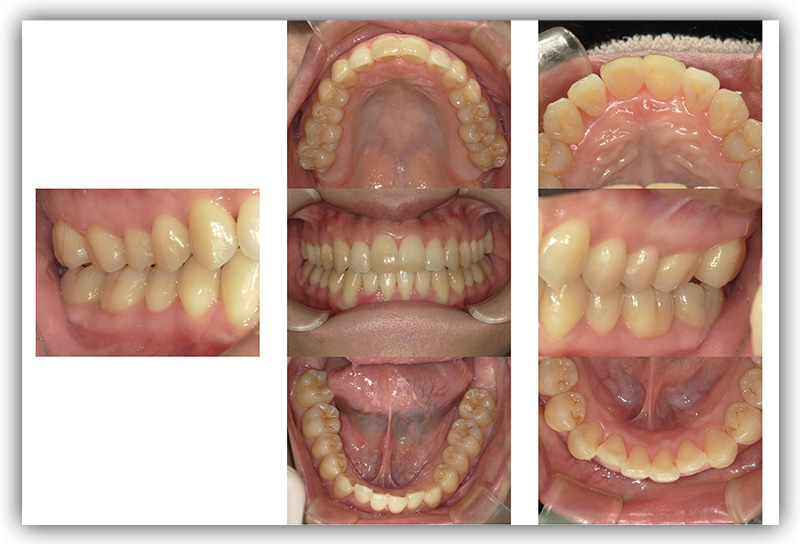

CASE_01

40代男性(インビザライン矯正+セラミック治療)

- 患者さん情報(年齢・性別)

- 40代 男性

- 主訴

- 歯並び、銀歯を白くしたい

- 治療箇所

- 10か所

- 治療方法

- 銀歯をセラミックに変更

- 費用

- インビザライン77万円

- セラミック10か所約80万円

- 治療期間

- インビザライン約1年

- セラミック治療10か所約8か月

- その治療によるリスク・副作用

- 歯肉退縮することがある

- 矯正中はしみたり、痛みを伴うことがある